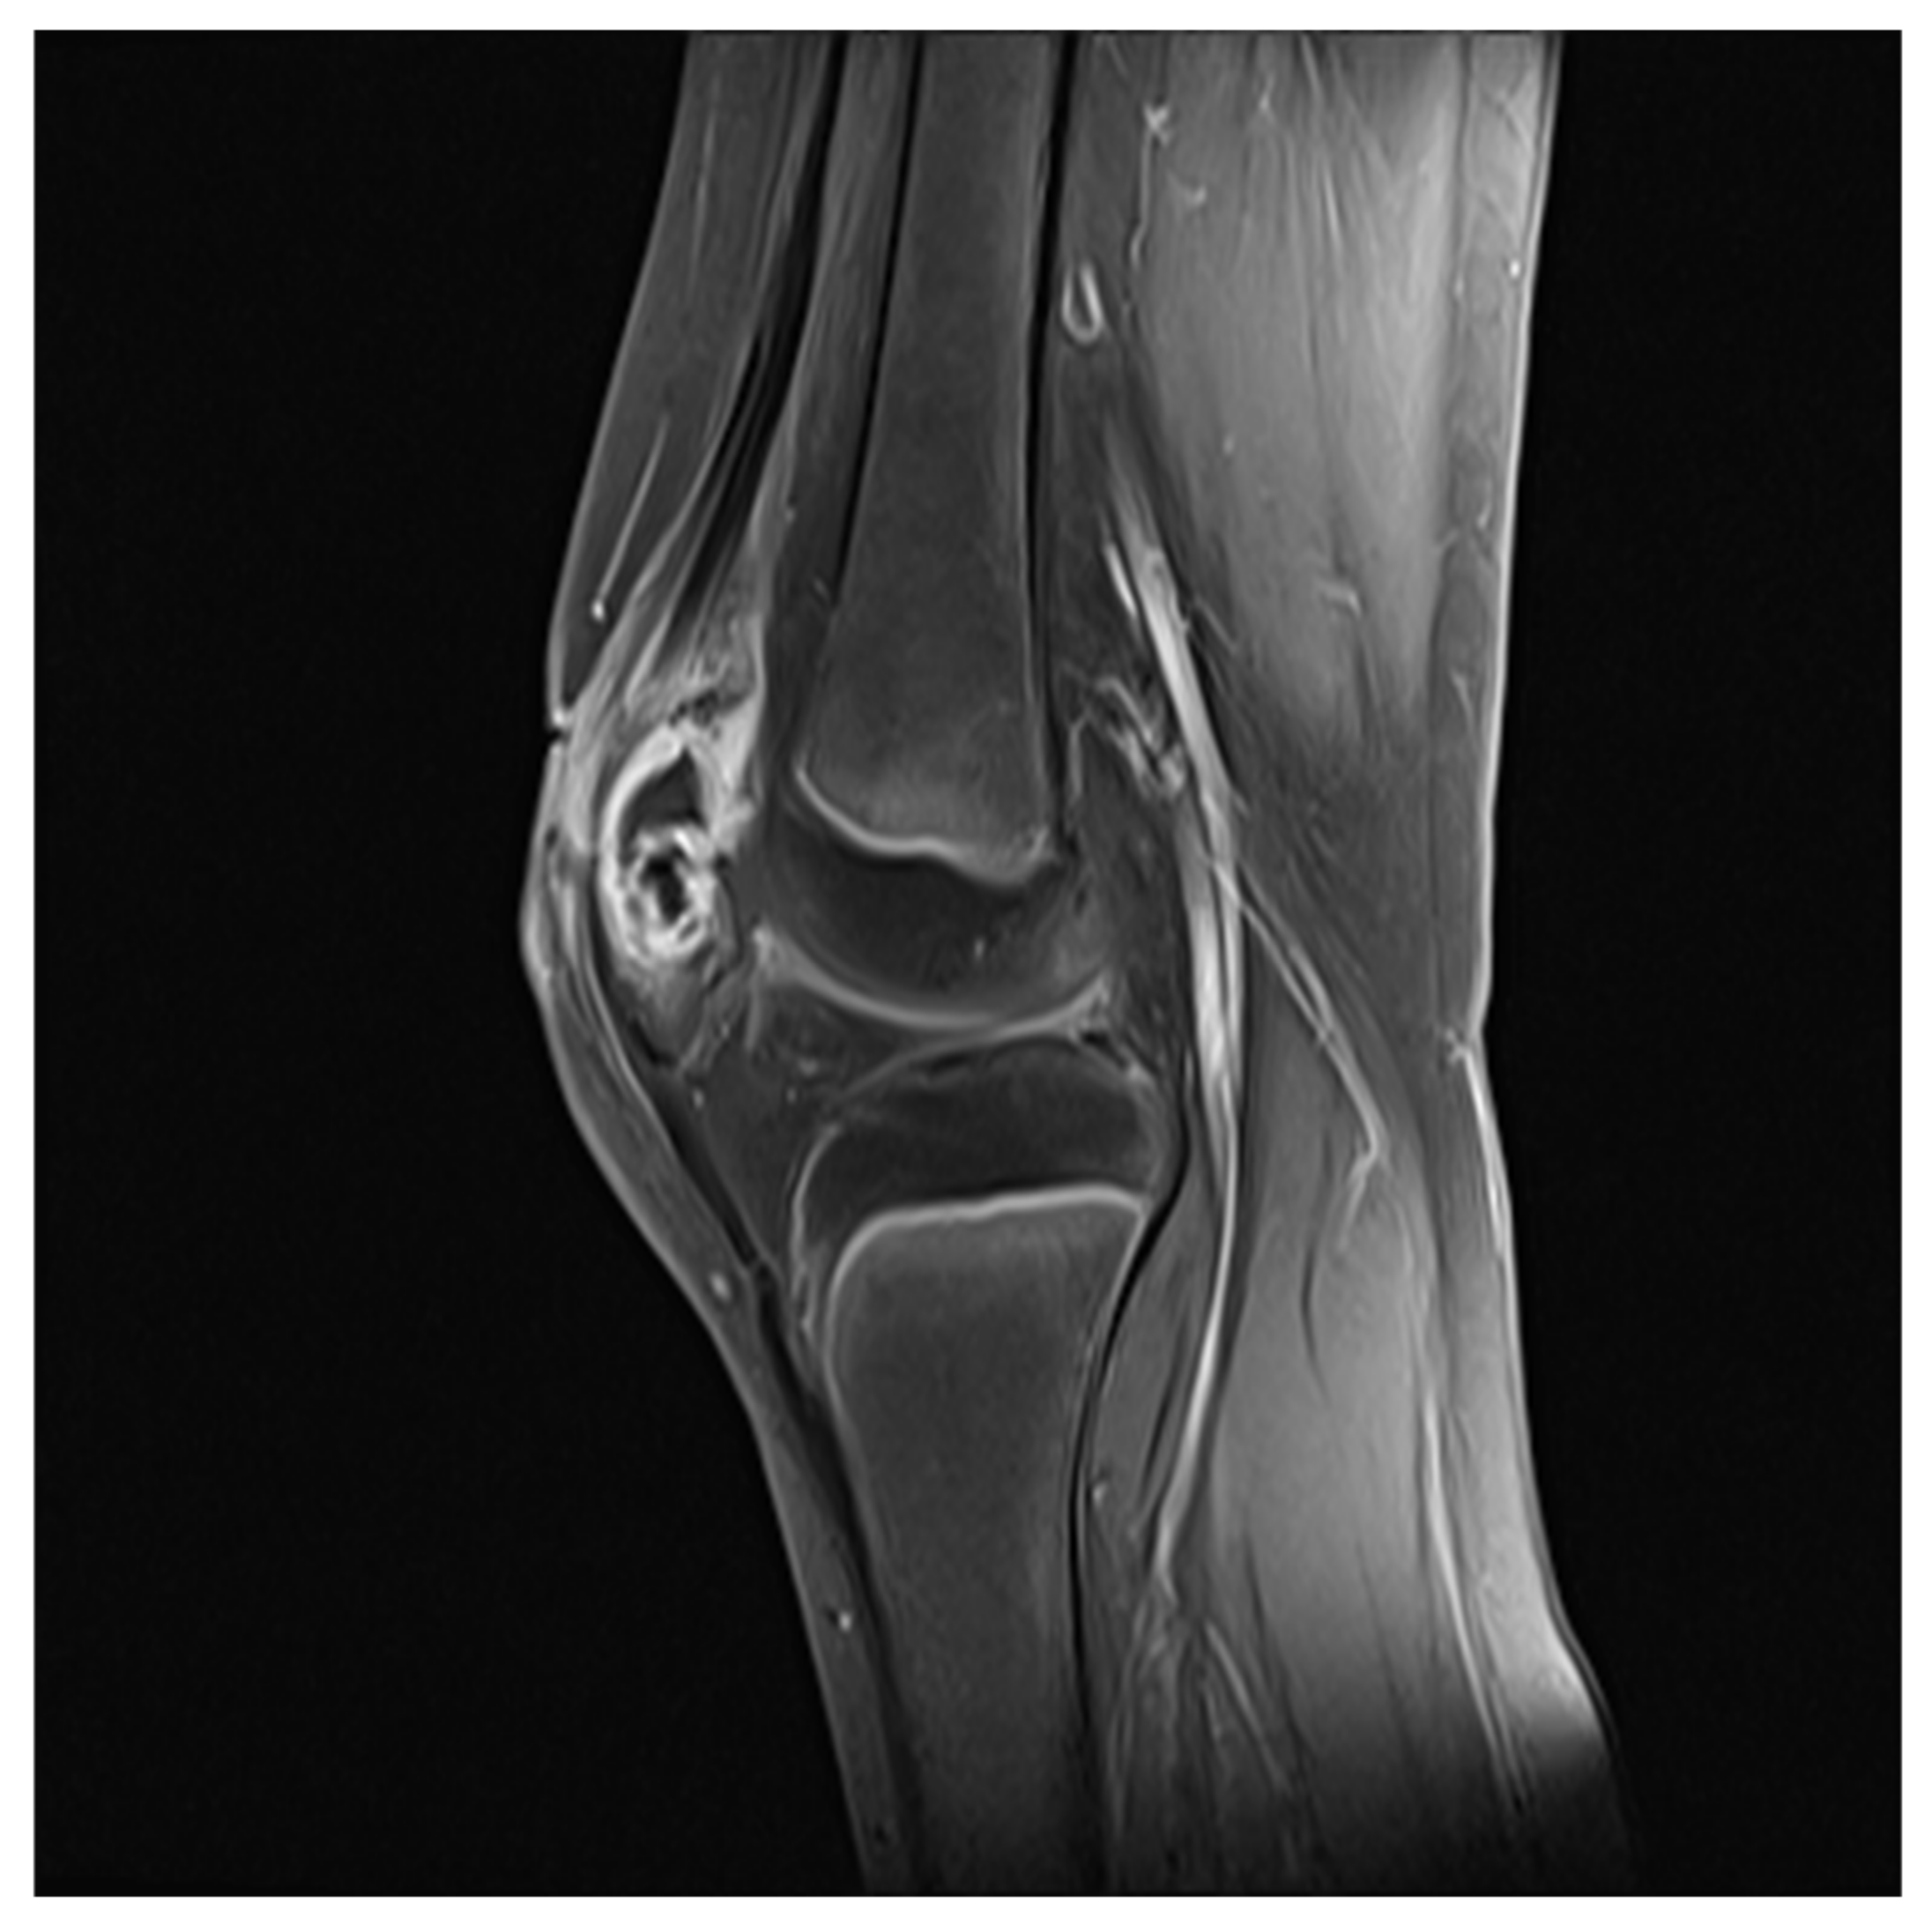

Patellar Osteomyelitis in a 9-Year-Old Patient with Chronic Granulomatous Disease: A Case Report

2. Case Report